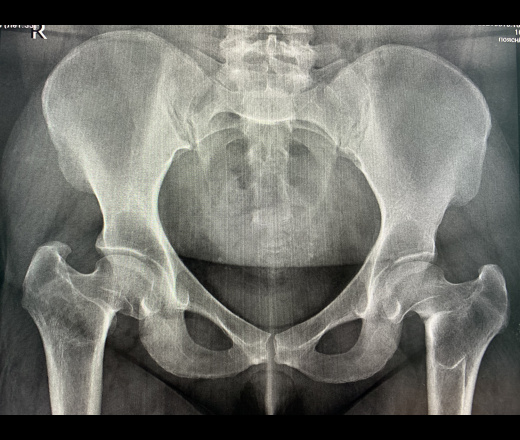

Рентген снимок женского таза.

На деле, мышцы , жир и кожные покровы получаются чуть ниже. На данном снимке присутсвуют сильные жировые отложения + сильный общий износ организма. Вероятно, у молодых особей в силу упругости связок и кожи вагинальная зона может быть чуть выше, а износ костей меньше.